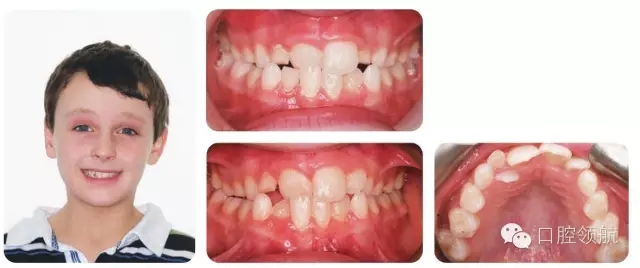

發(fā)育期牙列(病例2.7)

8歲的男性患者,處于混合牙列期,圖2.17上圖是當(dāng)時(shí)的咬合像,下圖是1年后的咬合像(正面和牙合面)。

如何描述該錯(cuò)牙合?

I類(lèi)切牙關(guān)系,UR1反。上下牙列均有擁擠,UR2腭側(cè)錯(cuò)位。